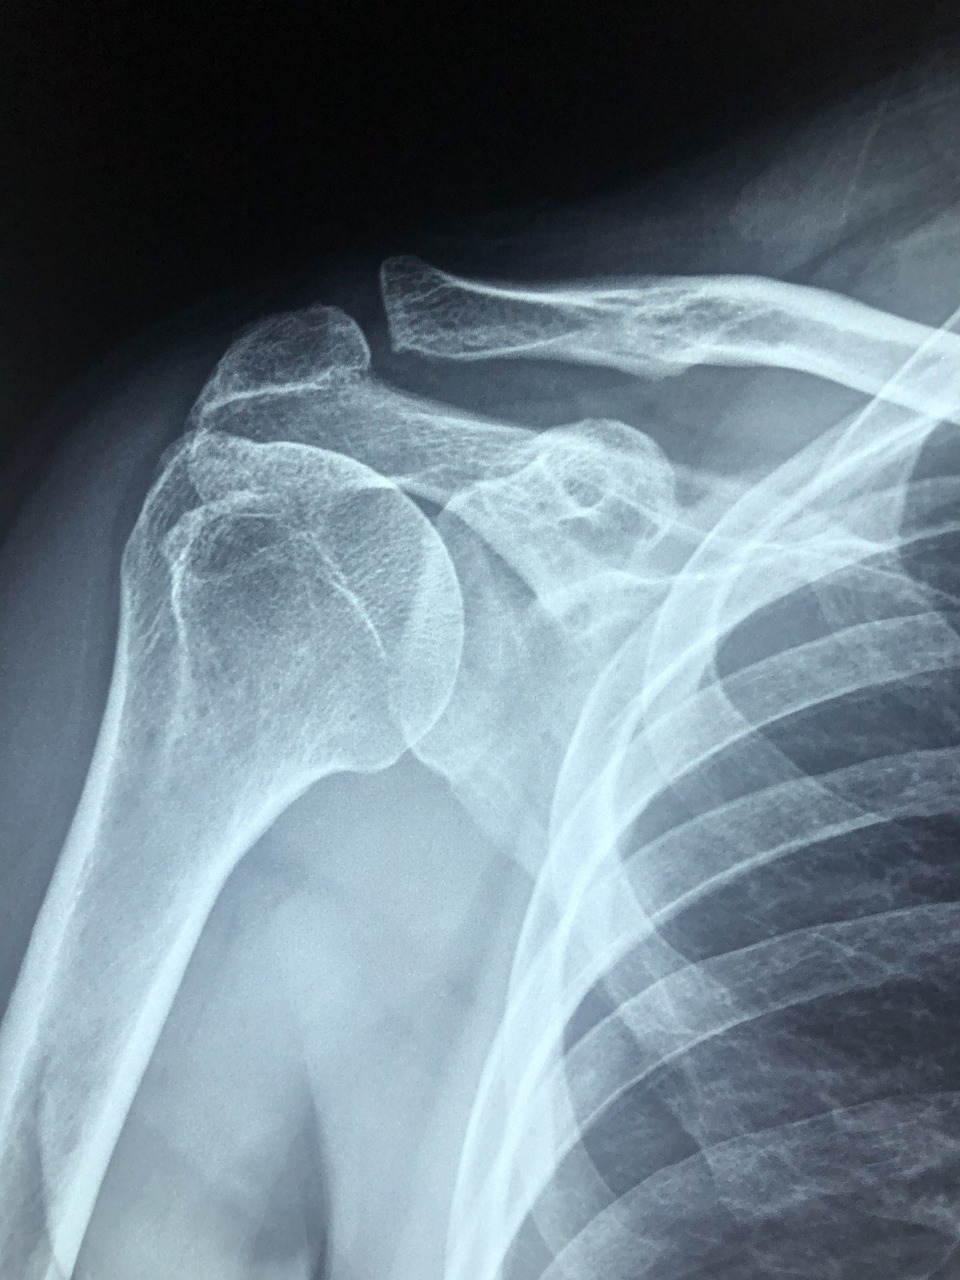

회전근개파열 수술은 파열된 어깨 힘줄을 봉합하는 수술입니다.

이 수술 후 바로 팔을 움직이면 봉합 부위가 다시 찢어질 수 있어요. 그래서 반드시 어깨 보조기를 착용해야 하죠.

특히 수술 직후 4~6주 동안은 손상 부위를 안정화시키는 초기 회복 기간으로, 이 시기 동안 움직임을 최소화하는 것이 필수예요.